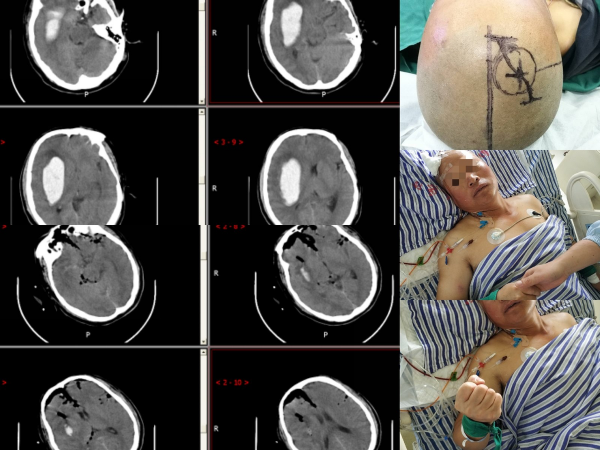

出血性腦梗塞又被稱為出血性腦梗塞、梗死後腦出血……,患者會因為一些致病因素導致腦血管破裂出血,出血灶壓迫患者腦實質引發一系列危害生命的問題。

長期高血壓會導致患者出現動脈粥樣硬化的問題,而血管變硬、變脆會影響心腦血管的彈性,當高速血流透過病變的血管時,就好像120邁速度的汽車行駛在年久失修的高速公路上,誰也不知道它下一秒會不會衝出柵欄,血液亦是如此,一旦血管經受不住血流衝擊,腦出血就此發生。

腦出血時我們一定要幫助患者減少出血的量,所以最好的方式就是讓患者採用側臥位,然後給他的頭部墊枕頭,記住此時千萬不要移動患者,以免出現更嚴重的出血,就地擺放即可,至於側臥位採用的是左側還是右側沒有關係,只要讓頭部高於身體即可。

腦出血需要醫護、家屬的共同努力,做到早發現、早搶救,只要發現及時,患者就有治癒的希望。治癒後該疾病的複發率高達40%,患者必須重視起來,飲食、生活方面多多注意。